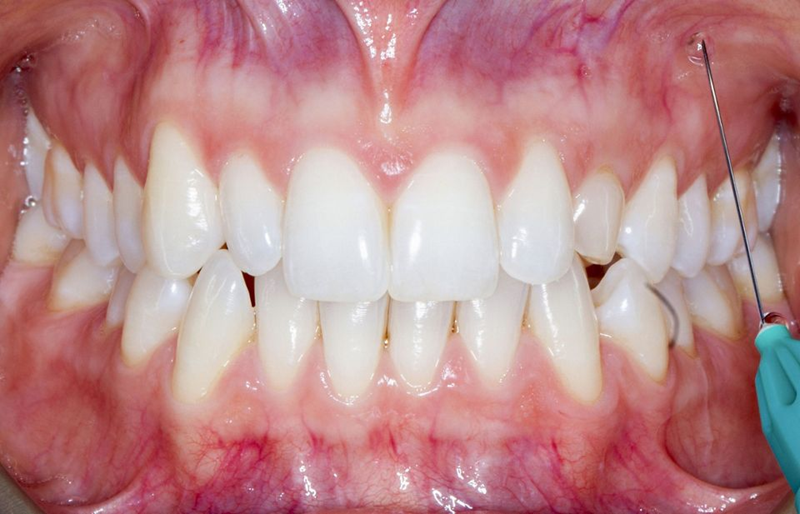

治疗结果

患者和我们的团队对最终结果在健康、美观和功能方面都非常满意。即使详细分析,也很难识别出最终的修复体(图63)。

Fig. 63: Frontal view of the final result.

在这一点上,我们可以说我们满足了患者的所有需求和期望,并且与基线情况相比(图 64),我们可以看到一个很大的改进。

Fig. 64: Before and after the treatment: Note how the smile of the patient was improved simply by...